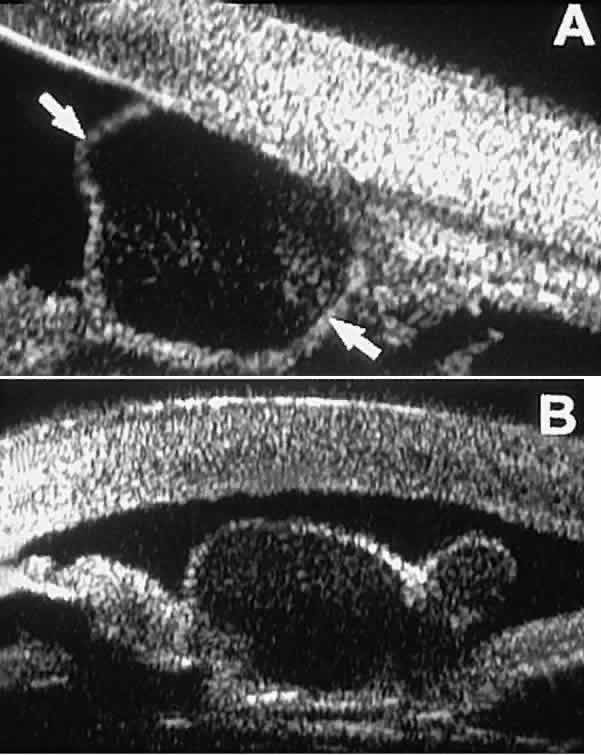

Postoperative UBM imaging of the anatomic changes caused by glaucoma surgery often helps to explain mechanisms of success and failure of the various surgical procedures (Fig. 12).3,4 After laser iridotomy, UBM can show whether the iridotomy is partial thickness (see Fig. 12A) or full thickness (see Fig. 12B) and whether the plane of curvature of the peripheral iris has changed compared with the pretreatment findings. After trabeculectomy (see Fig. 12C), UBM can show whether the scleral aperture is patent or blocked internally, whether the peripheral iridectomy is open or blocked, and whether the filtering bleb is flat, shallow, or deep.9 After tube shunt surgery (see Fig. 12D), UBM can show the position of the tip of the tube and whether its orifice is open or plugged.

Fig. 12. UBM features in glaucomatous eyes after treatment or filtering surgery. A. Incomplete peripheral iridectomy created by laser. B. Full-thickness peripheral iridectomy created by laser. C. Postoperative features of trabeculectomy including peripheral iridectomy, inner scleral defect, thin residual scleral flap, and overlying conjunctival filtering bleb. D. Tube shunt projecting radially into anterior chamber; note that the tube “shadows” deeper structures.

After any type of glaucoma filtering surgery,10 UBM can be used to detect and evaluate the extent of postoperative complications such as ciliochoroidal effusion and cyclodialysis.3,4 In ciliochoroidal effusion (Fig. 13A), UBM shows the ciliary body to be edematous and separated from the sclera by a sonolucent collection of supraciliary fluid. Many ciliochoroidal effusions that are too limited in extent to be detectable by indirect ophthalmoscopy and slit lamp biomicroscopy can be imaged by UBM. In cyclodialysis (see Fig. 13B), UBM shows a well-defined separation between the uveal tissue and the sclera in the region of the scleral spur. The width of the cleft is usually assessed best by means of limbus-concentric images through the region of interest.

Fig. 13. Complications of intraocular surgery. A. Postoperative ciliochoroidal effusion appears as slitlike spaces filled with serous fluid posterior to scleral spur. B. Postoperative cyclodialysis appears as complete separation of iris and ciliary body from sclera in region of scleral spur.